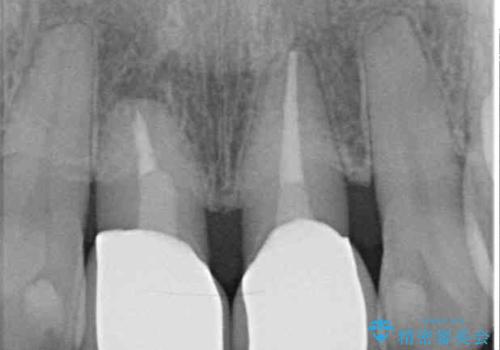

- 上の前歯の変色と、下の前歯のデコボコを気にして来院された患者様です。

前歯はオールセラミッククラウンに補綴することとしました。

補綴治療に先立ち、下顎前歯の部分矯正を行い、前歯の咬み合わせの安定性向上を図りました。

当初は上顎の補綴治療のみを希望されていましたが、奥歯にブリッジなど補綴物が多くあり、前歯も変色しているため、治療費が高額となってしまうことが懸念されました。